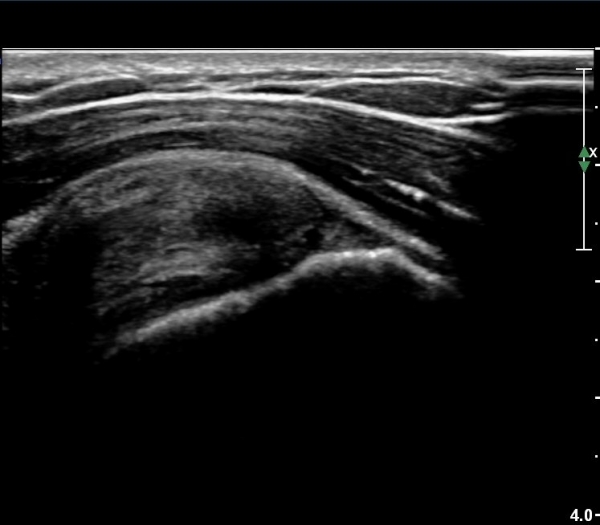

¾î±ú¸¦ ³»Àü, ³»È¸ÀüÇÑ »óÅ¿¡¼­ ±Ø»ó°ÇÁ¾´Ü¸é°Ë»ç»ó  ³»ÃøºÎ ÆÄ¿­ÀÌ °üÂûµÇ°í»çÁø 6, 7)

Ⱦ´Ü¸é°Ë»ç¿¡¼­ ±Ø»ó°Ç ³»ÃøºÎ ÆÄ¿­°ú ºÎÁ¾ÀÌ °üÂûµÈ´Ù(»çÁø 8), ŽÃËÀÚ¸¦ ¸»´ÜÀ¸·Î À̵¿ÇÏ´Ï

±Ø»ó°Ç ºÎÂøºÎ ÆÄ¿­ÀÌ ¶Ñ·ÈÇÏ´Ù(»çÁø 9).